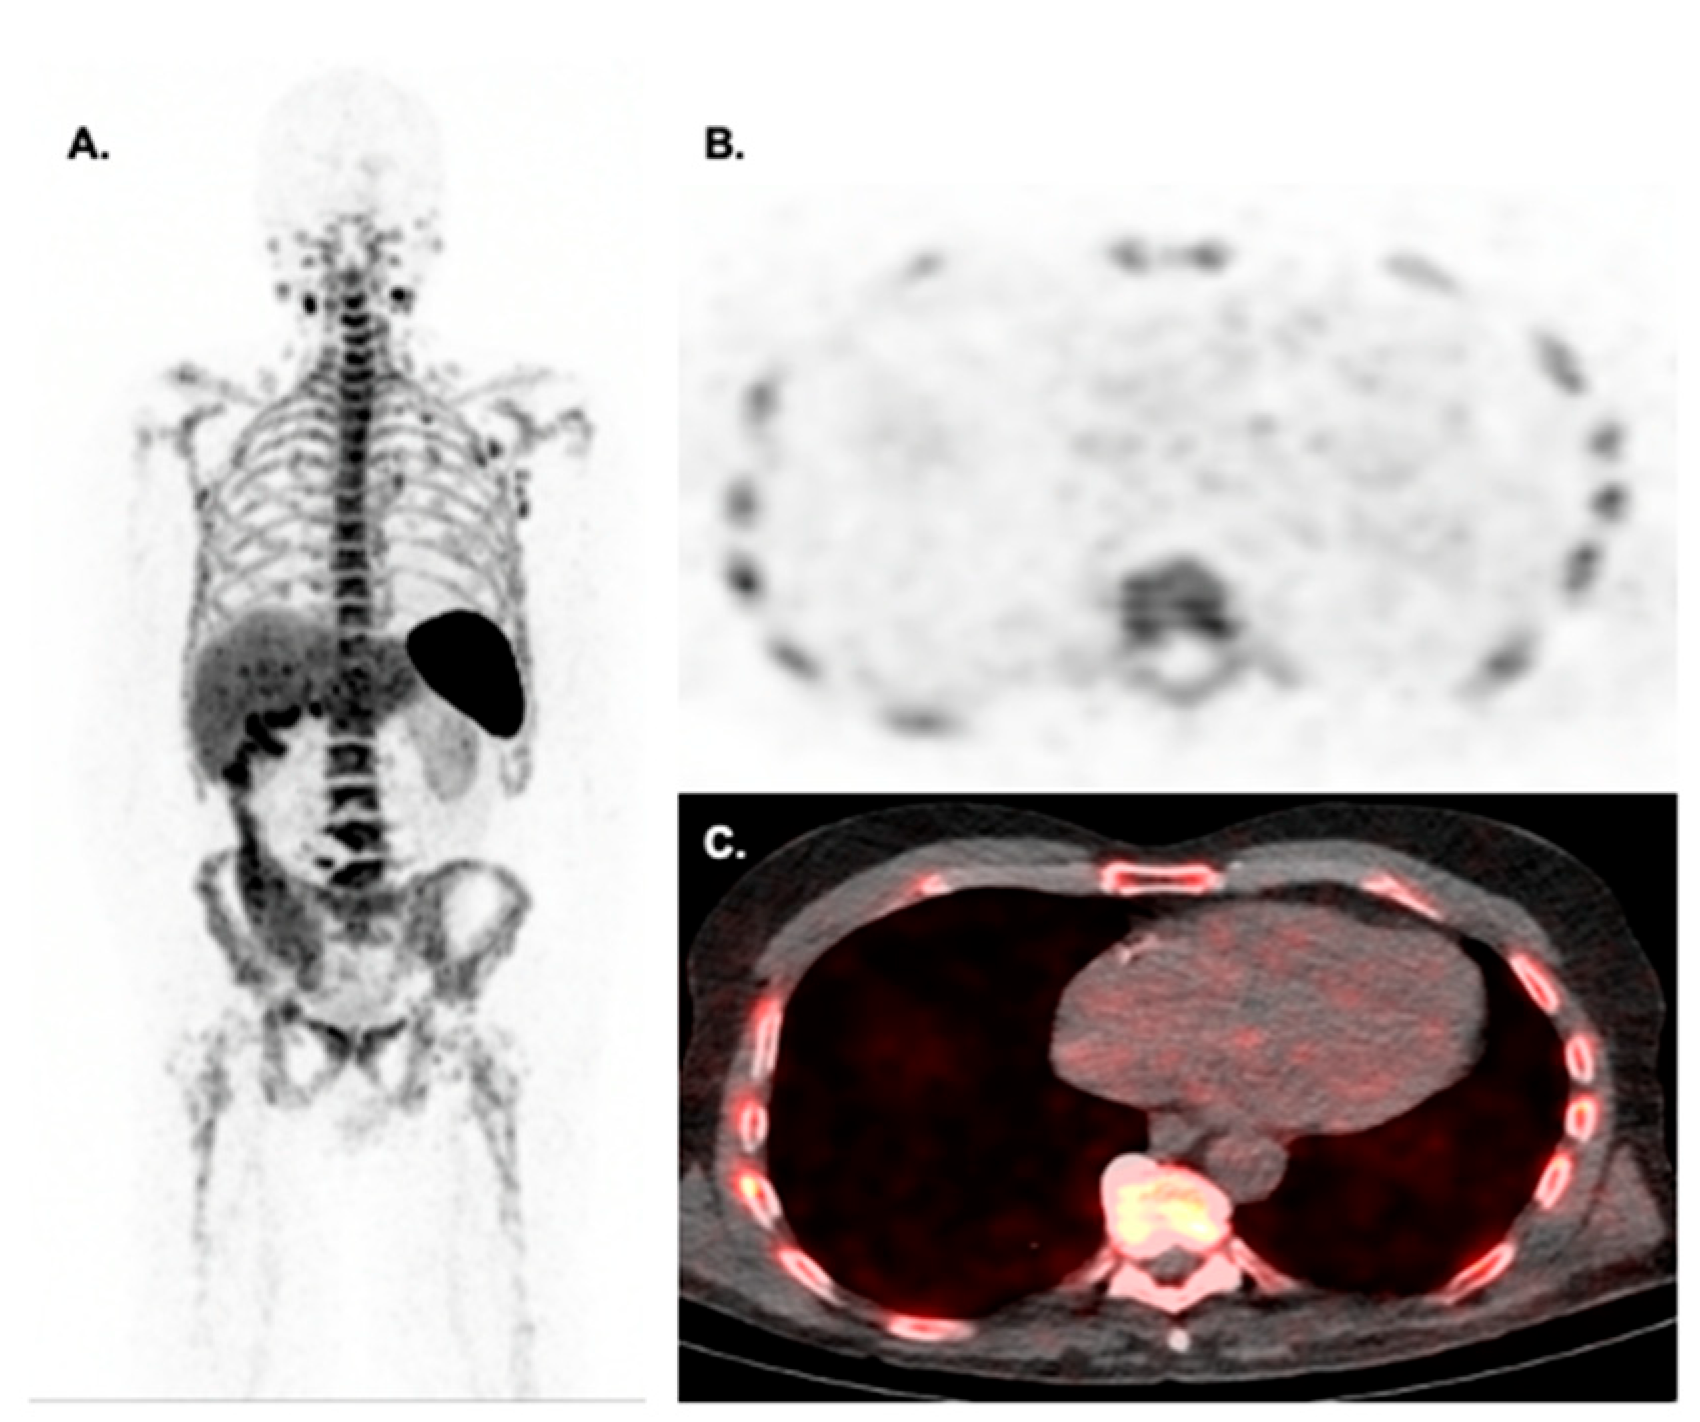

- Dreyfuss, A.D.; Goia, D.; Shoniyozov, K.; Shewale, S.V.; Velalopoulou, A.; Mazzoni, S.; Avgousti, H.; Metzler, S.D.; Bravo, P.E.; Feigenberg, S.J.; et al. A Novel Mouse Model of Radiation-Induced Cardiac Injury Reveals Biological and Radiological Biomarkers of Cardiac Dysfunction with Potential Clinical Relevance. Clin. Cancer Res. 2021, 27, 2266–2276. [Google Scholar] [CrossRef]